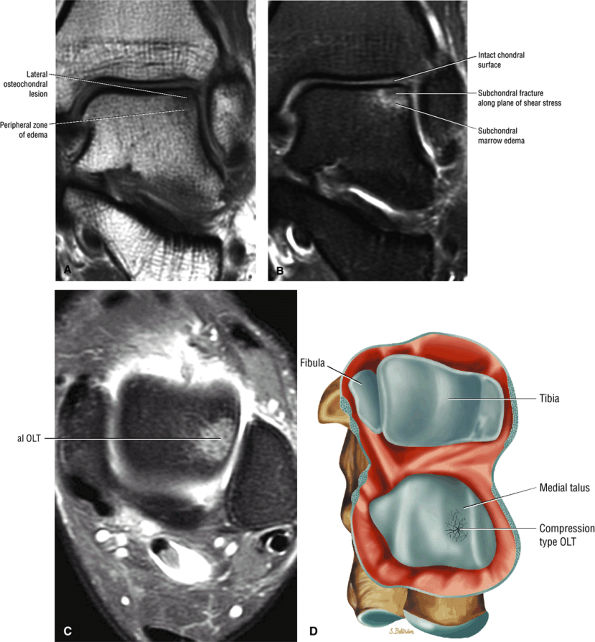

FIGURE 5.94 ● Lateral OLT with intact overlying chondral surface. Subchondral trabecular fracture and adjacent marrow edema are demonstrated on a coronal T1-weighted image (A). Mid-lateral talar dome location is shown with a cross-sectional area of reactive marrow edema. The edema associated with OLT should not be misinterpreted and result in overestimation of the area of trabecular bone involved. Coronal T1-weighted image. (B) Coronal FS PD FSE image. (C) Axial FS PD FSE image. (D) Color illustration with the capsule cut and the tibia and fibula reflected. Compression-type OLT corresponding with an area of subchondral trabecular compression in a stage I lesion.

|